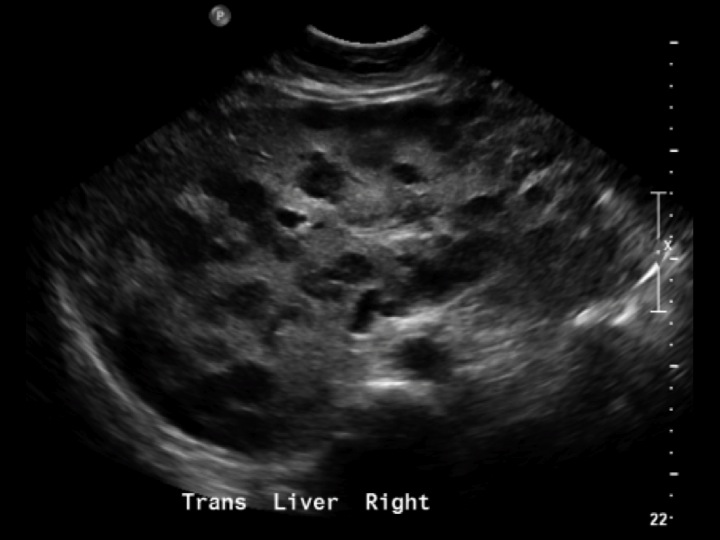

УЗИ лимфоузлов при лимфоме Ходжкина